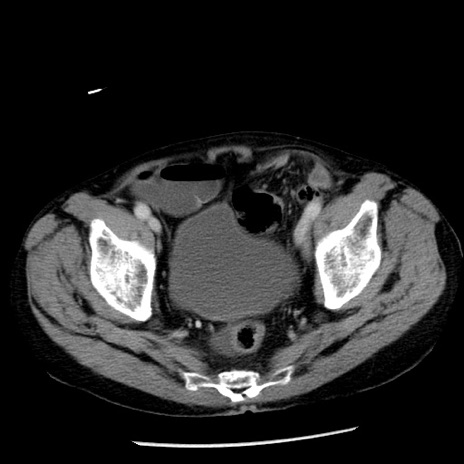

症例26(横断像)

【症例】80歳代男性

【主訴】嘔吐

【現病歴】昨晩2回嘔吐あり、今朝になっても嘔吐あり。来院。

【既往歴】胃潰瘍

【身体所見】意識清明、BT 37.6℃、BP 166/95mmHg、HR 100bpm、SpO2 97%、腹部:平坦・軟、腸蠕動音聴取良好、圧痛なし。

【データ】WBC 21900、CRP 1.46